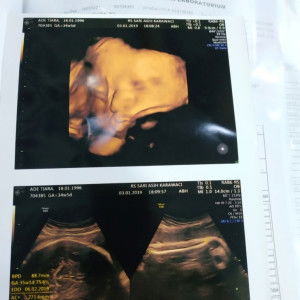

Ibu2 bsa bntu aku, obt sakit gigi dn bengkak gusi untk ibu hamil apa ya? Mohon bntuannya di jwab.🙏

Ibu hamil